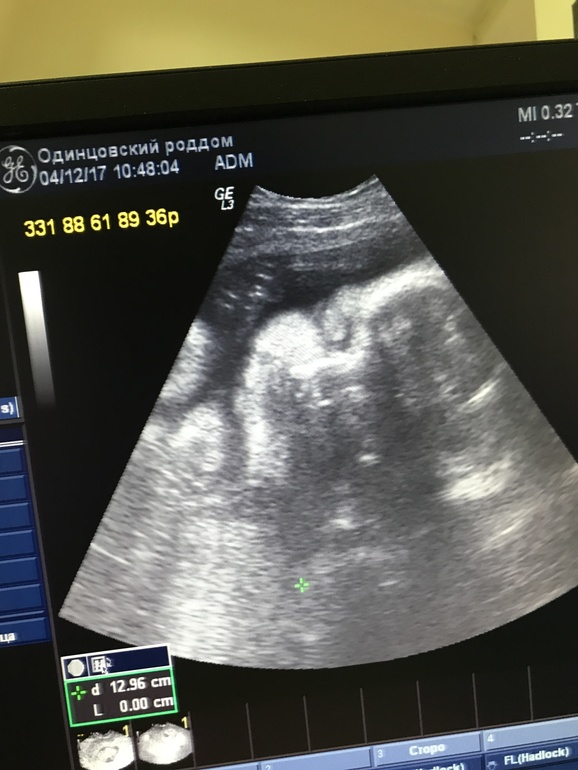

33недели + 3 дня

Сделала УЗИ во вторник, третье плановое. Так все хорошо, только есть однократное обвитие((((

Ну и под катом еще фотопуз и наш малыш❤️